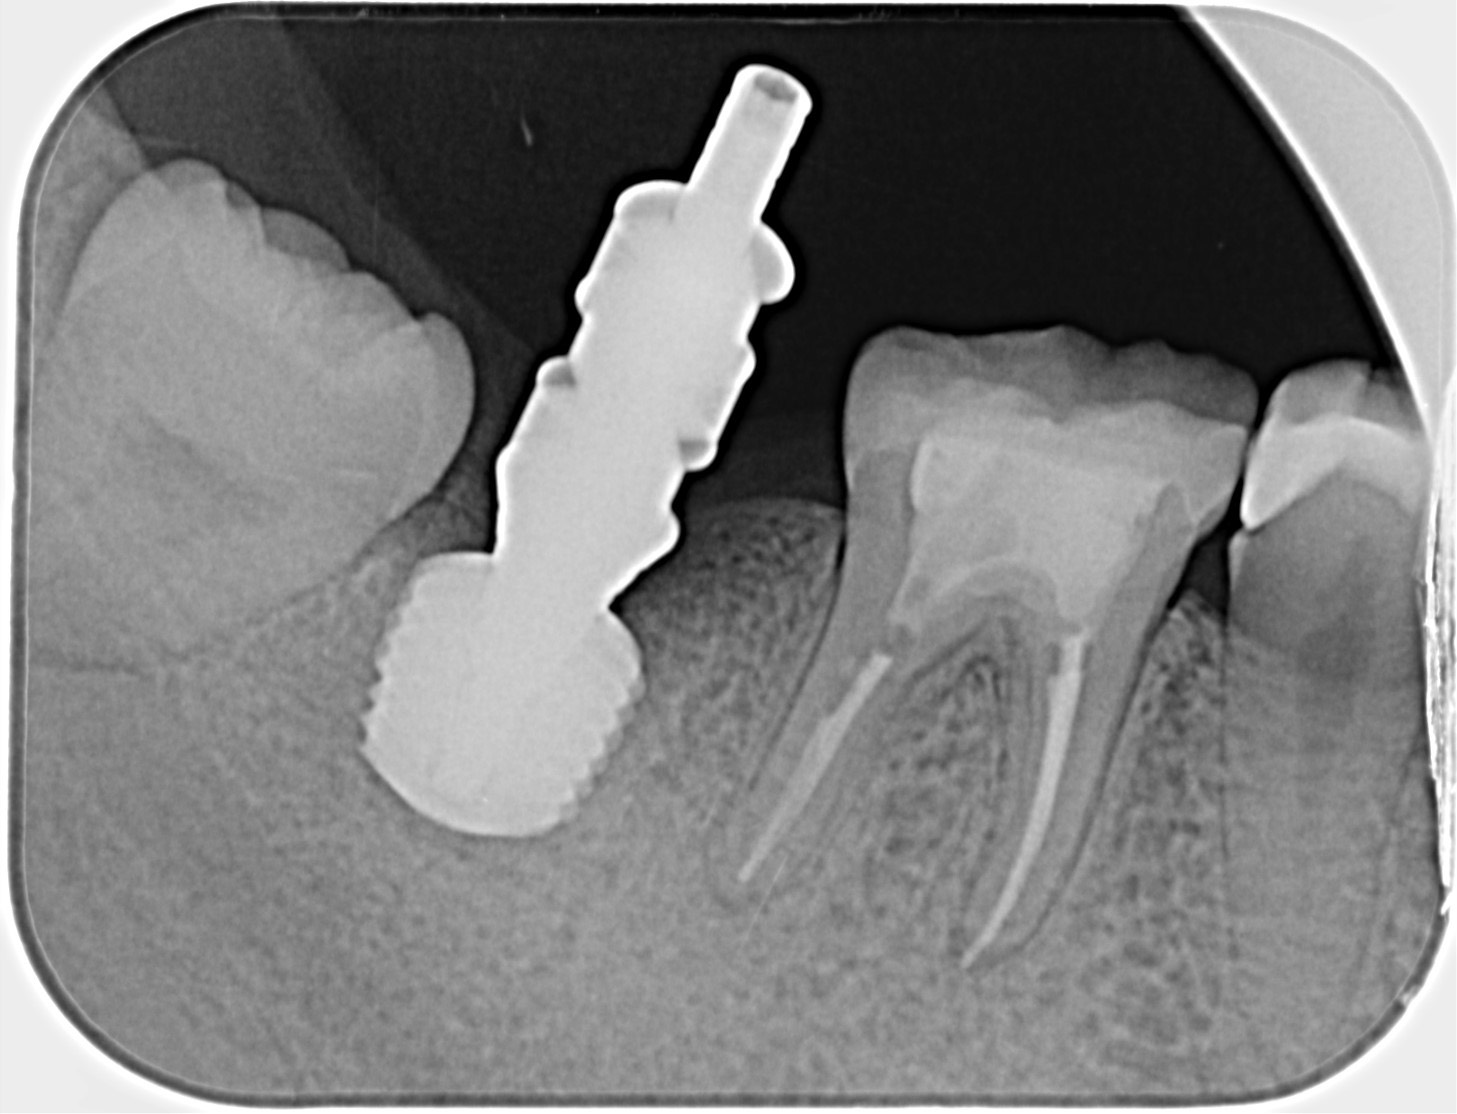

30代、女性、右下に違和感があることを健診中に申され、インプラント治療を行いました。

| 患者様の主訴 | 右下に違和感がある |

| 診断結果 | 右下7番歯根破折 |

| 治療内容 | 抜歯即時インプラント |

| 治療期間 | 8週間 |

| 治療費用 | ¥539,000(税込) |